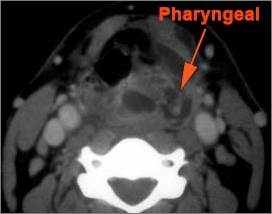

Retropharyngeal Lymph Nodes

There is reactive retropharyngeal lymphadenopathy. [Yes/No]

There is suppurative retropharyngeal lymphadenopathy. [Yes/No]

If there is suppurative retropharyngeal adenopathy what is the maximum short axis dimension of the largest suppurative node. MEASUREMENT [Yes/No]

There is related edema/abscess within the adjacent parapharyngeal/retropharyngeal spaces. [Yes/No]